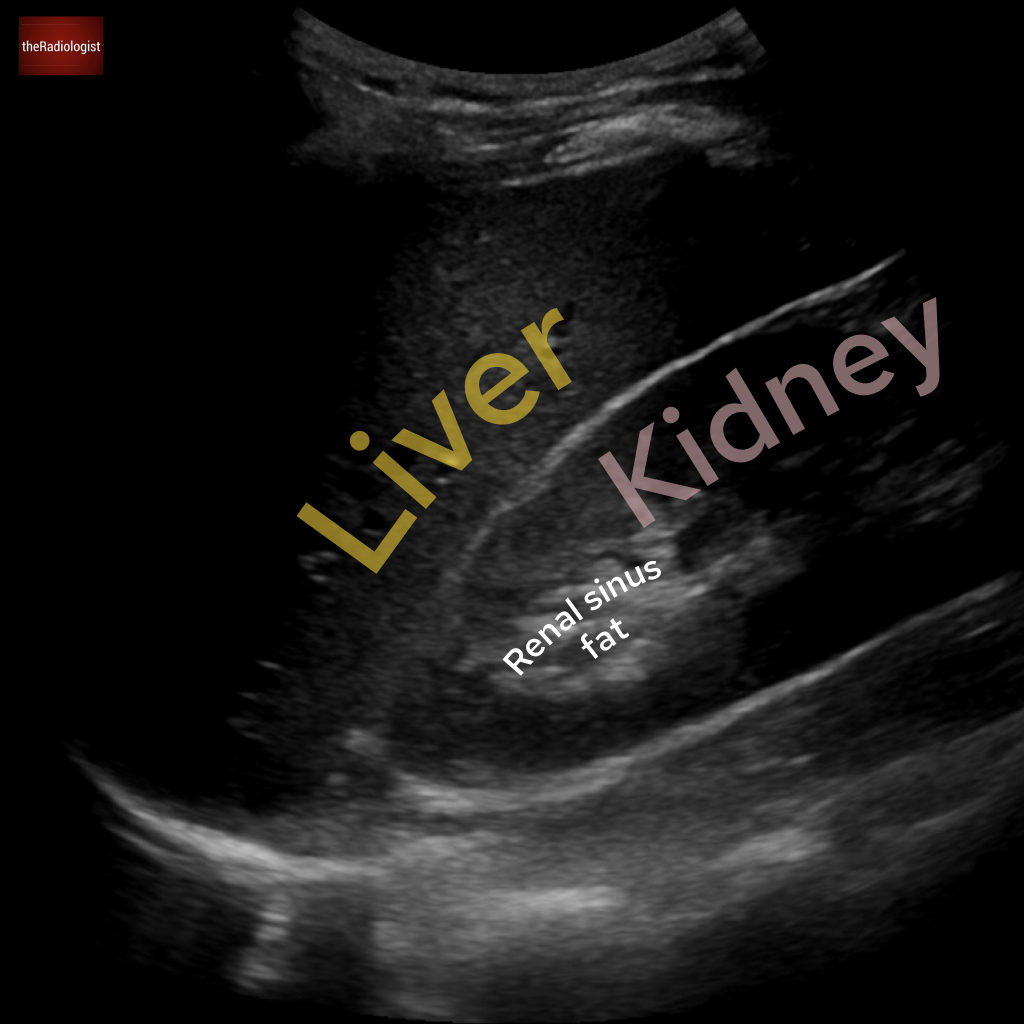

An abdominal ultrasound for this case. What is the arrow pointing at?

Choose one from the following: